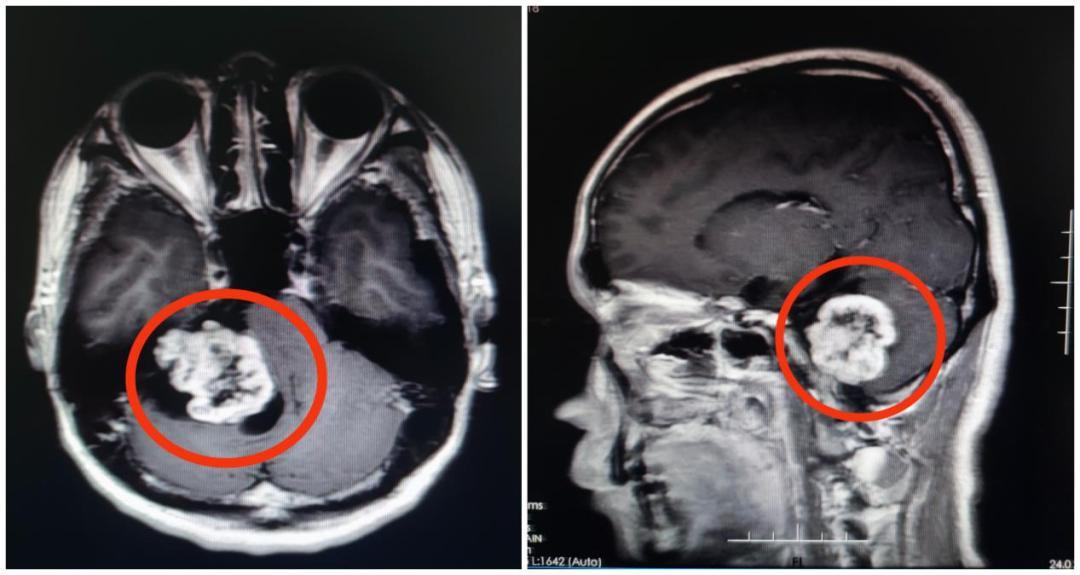

“从影像资料来看,怀疑是听神经瘤的可能性比较大。”该院副院长鲁明接诊时,发现一个鸡蛋大小的肿瘤正压着患者的内听道和脑干。除肢体乏力、面肌痉挛、头痛等症状外,还严重影响了他的听力。

完善术前准备,鲁明教授带领神经外五科团队为患者行右侧桥小脑角占位性病变切除术,全切肿瘤。术后病理结果证实为听神经瘤。